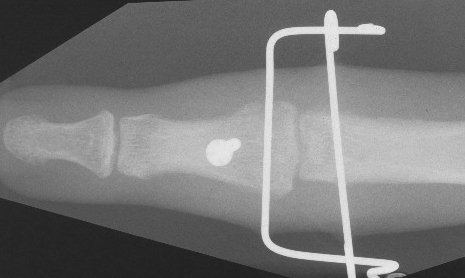

Clinical Example: PIP fracture dislocation treated with force couple splint

Proximal interphalangeal joint fracture dislocation is a common and difficult injury. There are many possible treatment techniques. Here, the force couple splint method was used.